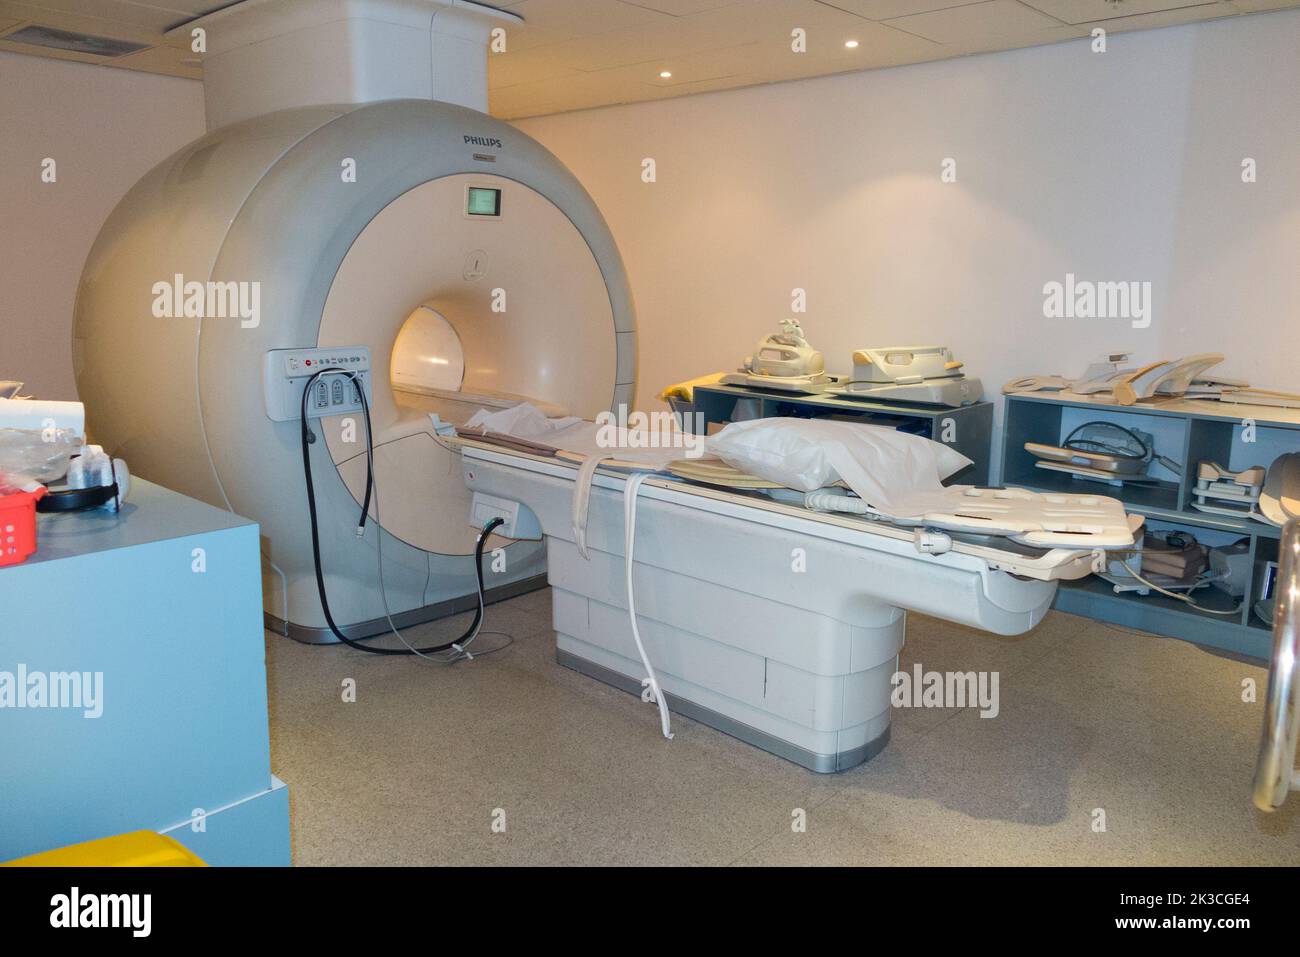

Un scanner IRM (considéré comme une machine IRM Philips Achieva) est un appareil IRM du corps entier destiné à l'examen des patients, dans un hôpital, utilisé pour les patients privés et non médicaux. Banque D'Imageshttps://www.alamyimages.fr/image-license-details/?v=1https://www.alamyimages.fr/un-scanner-irm-considere-comme-une-machine-irm-philips-achieva-est-un-appareil-irm-du-corps-entier-destine-a-l-examen-des-patients-dans-un-hopital-utilise-pour-les-patients-prives-et-non-medicaux-image484010636.html

Un scanner IRM (considéré comme une machine IRM Philips Achieva) est un appareil IRM du corps entier destiné à l'examen des patients, dans un hôpital, utilisé pour les patients privés et non médicaux. Banque D'Imageshttps://www.alamyimages.fr/image-license-details/?v=1https://www.alamyimages.fr/un-scanner-irm-considere-comme-une-machine-irm-philips-achieva-est-un-appareil-irm-du-corps-entier-destine-a-l-examen-des-patients-dans-un-hopital-utilise-pour-les-patients-prives-et-non-medicaux-image484010636.htmlRM2K3CGE4–Un scanner IRM (considéré comme une machine IRM Philips Achieva) est un appareil IRM du corps entier destiné à l'examen des patients, dans un hôpital, utilisé pour les patients privés et non médicaux.

Un scanner IRM (considéré comme une machine IRM Philips Achieva) est un appareil IRM du corps entier destiné à l'examen des patients, dans un hôpital, utilisé pour les patients privés et non médicaux. Banque D'Imageshttps://www.alamyimages.fr/image-license-details/?v=1https://www.alamyimages.fr/un-scanner-irm-considere-comme-une-machine-irm-philips-achieva-est-un-appareil-irm-du-corps-entier-destine-a-l-examen-des-patients-dans-un-hopital-utilise-pour-les-patients-prives-et-non-medicaux-image484010631.html

Un scanner IRM (considéré comme une machine IRM Philips Achieva) est un appareil IRM du corps entier destiné à l'examen des patients, dans un hôpital, utilisé pour les patients privés et non médicaux. Banque D'Imageshttps://www.alamyimages.fr/image-license-details/?v=1https://www.alamyimages.fr/un-scanner-irm-considere-comme-une-machine-irm-philips-achieva-est-un-appareil-irm-du-corps-entier-destine-a-l-examen-des-patients-dans-un-hopital-utilise-pour-les-patients-prives-et-non-medicaux-image484010631.htmlRM2K3CGDY–Un scanner IRM (considéré comme une machine IRM Philips Achieva) est un appareil IRM du corps entier destiné à l'examen des patients, dans un hôpital, utilisé pour les patients privés et non médicaux.